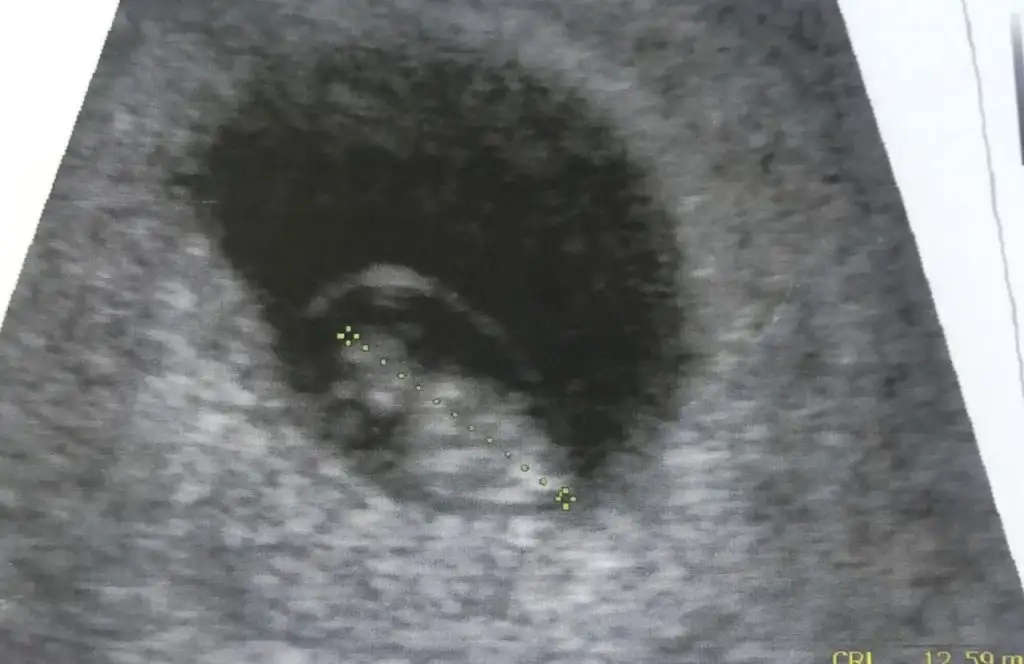

Evet burdada plesentası solda erkek bebek tabi nub için 11 yada 12 hafta paylaşınBenimde sata gore 8+4 tu ama doktorum 9+3 dedi ondrn gidiyo uzun boylu olcsk dedi kese sekline gore yorumlayabiliyonuzmu yoksa 12.haftaninmi usg sini atmam gerekiyor

Karından ise kız vajinal bakıldı ise asıl solmuş buna görede solda görünüyor erkekEki Görüntüle 2597248 Kızlar merhaba ben bu teoriyi karıştırdım anlayan varsa benim bebişede yorum yapabilirmisiniz6+1 şuan

Teşekkür ederimKarından ise kız vajinal bakıldı ise asıl solmuş buna görede solda görünüyor erkek

eklediğim fotolar vajinal ultrasondan ve burada 5+4 haftalık:)

Ben kese konumunu pek tuttugunu sanmıyorum ben nub tahmini yapıyorum 11 yada 12 hafta olmalı kesede yolk saç nerde ise yani sag tarafta hafif kabarık beyaz parlak alan sagda tabi siz vajinal bakıldıgı için asıl solda olmuş oluyor karından bakılınca asıl sol olmuş olacaktı ve erkekAyy çok teşekkür ederim en azından fikir verdiniz bana sağlıkla gelsin inşallah :) peki neye göre sağda ve ya solda diyoruz onu da sorsam size sanırım anlıyorsunuz bu konudan :)